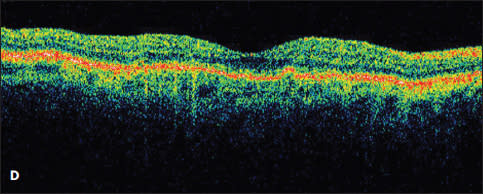

Figure 5. A patient with a serous PED was observed at presentation (A) and developed subretinal fluid three months later (B). Treatment was offered at three months, but the patient declined until a PED developed in the fellow eye 13 months later (C). At that time, the patient underwent intravitreal treatment with bevacizumab, with resolution of the subretinal fluid and a decrease in height of the PED (D). The patient’s vision was 20/32 both before and after treatment.

Case 5. The desire to avoid the risk of an RPE tear led one patient to refuse anti-VEGF therapy for more than a year and a half. This 69-year-old man presented with a large serous PED in the right eye, resulting in decreased vision from 20/20 to 20/126 (Figure 5A). There was no associated intraretinal or subretinal fluid on OCT, and due to the ability to correct his vision comfortably with a hyperopic refraction, observation with close follow-up was chosen.

Three months later, his vision remained 20/32, but subretinal fluid was noted on OCT (Figure 5B). Treatment was recommended, but the patient refused therapy. On multiple return visits, the patient continued to decline treatment. Sixteen months after his initial presentation, he developed metamorphopsia in his left eye, and a new serous PED was seen on OCT. The PED in his right eye had a stable cuff of subretinal fluid (Figure 5C).

At this point the patient consented to treatment with intravitreal bevacizumab in the right eye. After three injections, the subretinal fluid resolved, and the PED decreased slightly in apical height (Figure 5D). His vision remained unchanged at 20/32 throughout treatment.